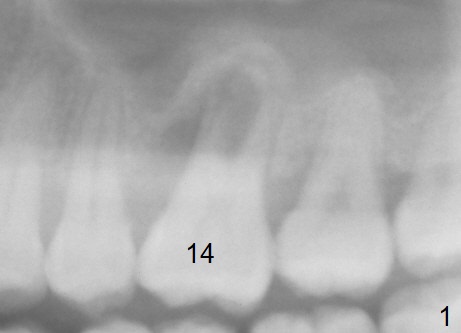

A 41-year-old man has had severe periodontitis at #14 for the last 11 years (Fig.1-3). Finally the tooth is mobile. Draw blood for PRF membrane (x4). After use of Magic Drill with 3 mm stopper, tap Magic Lifter for sinus lift. Insert 1-2 PRF membrane(s) and Vanilla graft prior to further osteotomy with UF drills until 4.5 or 5 mm. Insert tap drill for primary stability. If it fails, switch to IBS dummy implants.